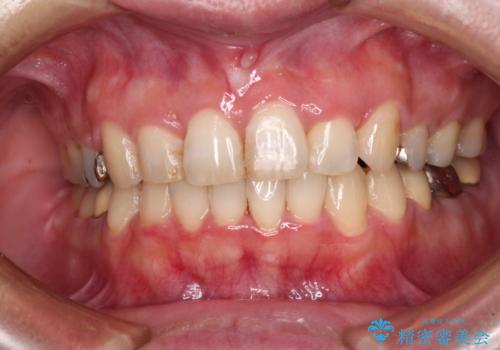

[ メタルフリー治療 ] 金属のない口腔内にしたい

![[ メタルフリー治療 ] 金属のない口腔内にしたいの症例 治療前](https://seimitsushinbi.jp/wp/wp-content/uploads/2021/09/2a134eb6522ae423858539412c8101be-500x350.jpg?v=1632299928)